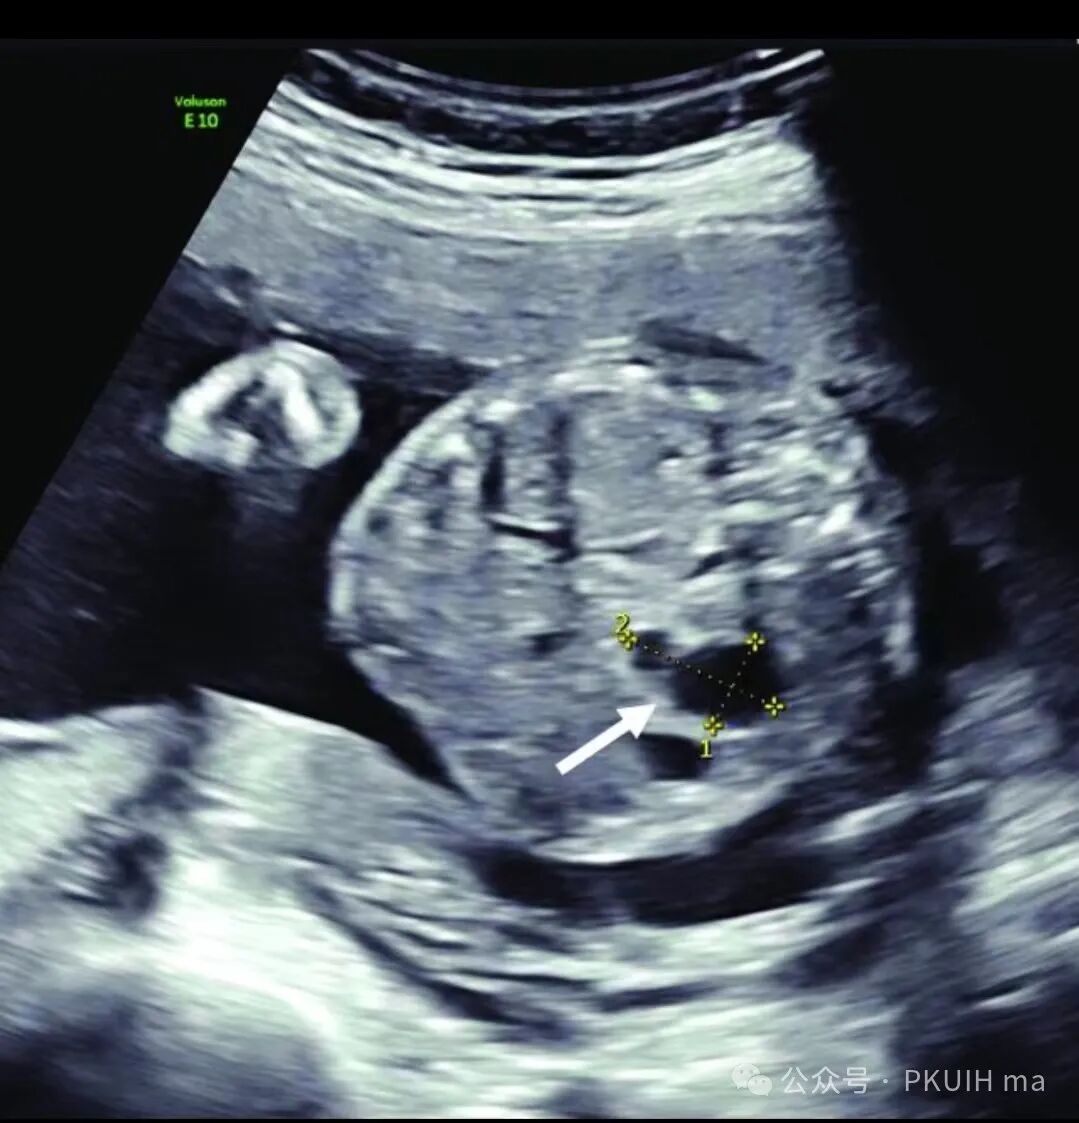

上两张图(第二张是37周)是一例在30周发现的肝囊肿,在随后观察中囊肿一直无变化